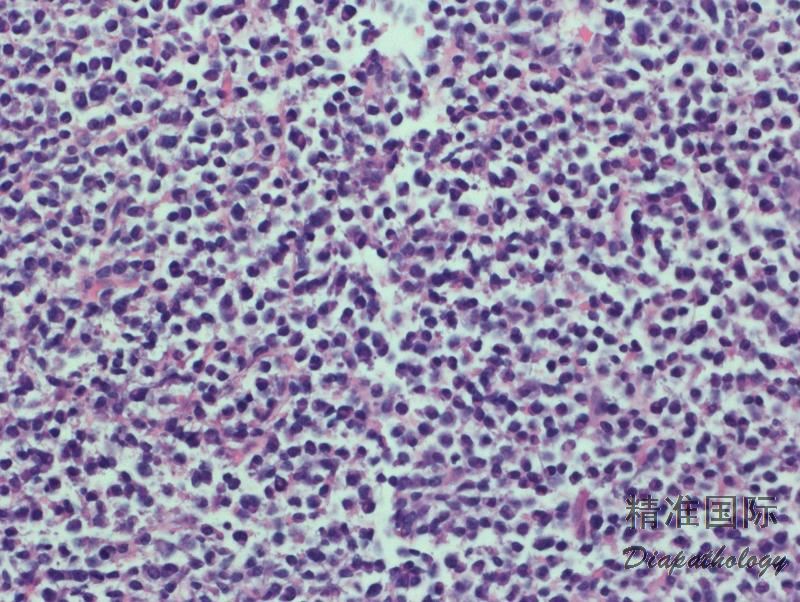

- 外周血可见循环肿瘤细胞和红细胞成钱串样重叠;骨髓几乎总是受侵犯,非小梁旁或小梁旁, 间质或弥漫侵润;淋巴结受侵以副皮质区为明显,可累及整个淋巴结。肿瘤细胞由小淋巴细胞、浆淋巴细胞和浆细胞谱系组成,可见 Dutcher 或 Russell 小体。肥大细胞数增加。

- 免疫组化和流式细胞 CD20 等 B 细胞抗原阳性,轻链染色或原位杂交揭示单克隆浆淋巴细胞或浆细胞。